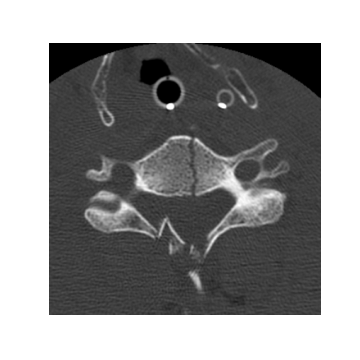

Fig. 2: Windowing of a given cervical spine CT image (in Hounsfield units (HU)) according to the following rules: 1) Soft tissue window (w1=300;c1=80formulae-sequencesubscript𝑤1300subscript𝑐180w_{1}=300;c_{1}=80); 2) Standard bone window (w2=1,800;c2=500formulae-sequencesubscript𝑤21800subscript𝑐2500w_{2}=1,800;c_{2}=500); 3) Gross bone window (w3=650;c3=400formulae-sequencesubscript𝑤3650subscript𝑐3400w_{3}=650;c_{3}=400).

Each pixel xi𝐱nsubscript𝑥𝑖subscript𝐱𝑛x_{i}\in\mathbf{x}_{n} is a quantitative representation of the radiodensity of different substances in the scanning area where 1,000xi3,000formulae-sequenceless-than-or-similar-to1000subscript𝑥𝑖less-than-or-similar-to3000-1,000\lesssim x_{i}\lesssim 3,000[7]. Fractures of the cervical spine are heterogeneous in their location, type, and composition. They are defined as a break in at least one bone in the cervical spine. The cervical spine can be malaligned as a result of a fracture and/or a ligamentous injury. Both fractures and ligaments injuries can be associated with localized bleeding and soft tissue swelling. In consultation with a panel of radiologists, three window width and center schemes are chosen to enhance cervical spine bone and surrounding tissues, which are soft tissue window (w1=300;c1=80)formulae-sequencesubscript𝑤1300subscript𝑐180(w_{1}=300;c_{1}=80), standard bone window (w2=1,800;c2=500)formulae-sequencesubscript𝑤21800subscript𝑐2500(w_{2}=1,800;c_{2}=500), and gross bone window (w3=650;c3=400)formulae-sequencesubscript𝑤3650subscript𝑐3400(w_{3}=650;c_{3}=400). Figure 2 shows the corresponding functions to the proposed windowing schemes to map xisubscript𝑥𝑖x_{i} to three different values x~i(1)superscriptsubscript~𝑥𝑖1\tilde{x}_{i}^{(1)}, x~i(2)superscriptsubscript~𝑥𝑖2\tilde{x}_{i}^{(2)}, x~i(3)superscriptsubscript~𝑥𝑖3\tilde{x}_{i}^{(3)}. The represented image with the gross bone window 𝐱~n(3)superscriptsubscript~𝐱𝑛3\tilde{\mathbf{x}}_{n}^{(3)} is then used to crop the images with 5%percent55\% margin from each side of detected cervical spine using Otsu’s method [8]. The cropped images are normalized and resized (padded with zero if not square) to 384×384384384384\times 384.